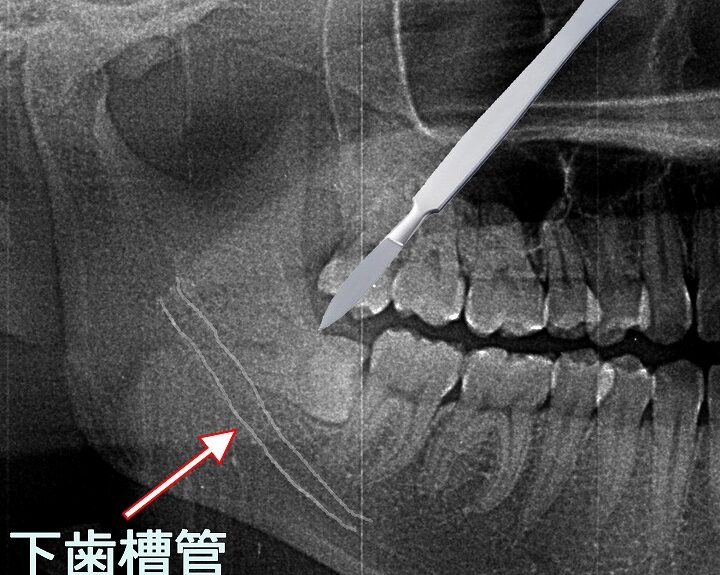

私たちの口腔健康において、埋まってる親知らず どうやって抜くかは重要なテーマです。多くの人がこの問題に直面しその対処法を探しています。特に親知らずが正しく生えてこない場合、痛みや感染症を引き起こす恐れがあります。このブログでは、埋まった親知らずの抜歯方法と気を付けるべき注意点について詳しく解説します。

まずは、埋まっている親知らずとは何か、その影響について理解を深めていきましょう。そして具体的な抜歯手順や術後のケアについても触れていきます。私たちが知識を持つことで、不安を軽減し安心して治療に臨むことができます。皆さんはこの問題で悩んだことがありますか?さあ、一緒に解決策を見つけていきましょう。